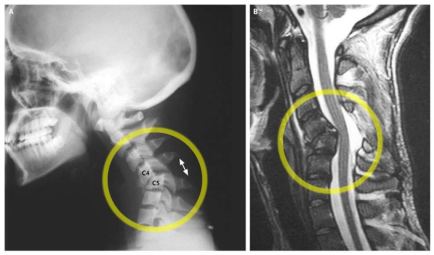

This is not her actual scan but it is pretty similar to what we saw on hers, though hers is a few vertebra below the one in the scan. Notice the C4 vertebra is not aligned with C5 in the photo on the left:

This certainly explains why her pain keeps getting worse; this has probably been gradually happening since late November when her recovery from surgery started feeling worse instead of better.